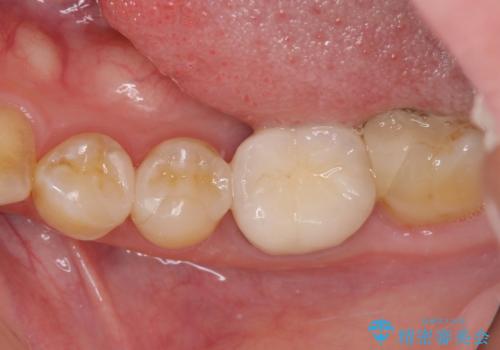

精密に型取りを行ったセラミックインレーを装着したことで、治療後にはしみたり痛んだりという症状は治まりました。